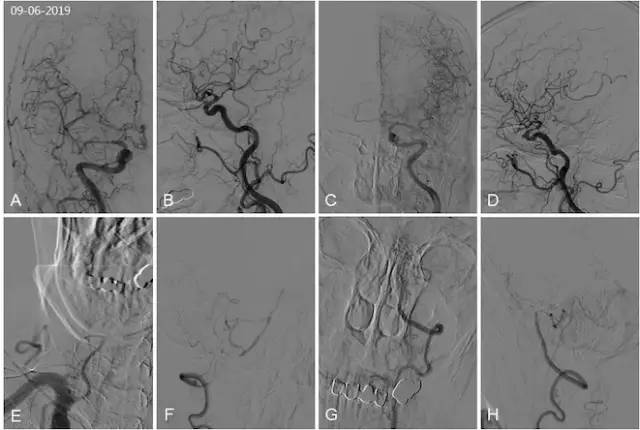

DSA(2019-09-06):右大脑后动脉为胚胎型大脑后动脉,右大脑后动脉P1段发育缺如,未见基底动脉尖显影(图4A,B);左后交通动脉发育不良,双小脑上动脉逆向显影(图4C,D);右锁骨下动脉开口处中度狭窄,右侧椎动脉自V3-V4移行处闭塞,右椎动脉V3段穿支与右小脑后下动脉吻合,向基底动脉供血,可见基底动脉管腔粗细不均,右小脑后下动脉起始处狭窄(图4E,F)。左椎动脉造影示左椎动脉发出小脑后下动脉以远闭塞,通过脊髓前动脉及小脑后下动脉分支与基底动脉吻合向基底动脉代偿供血,基底动脉显影欠佳(图4G,H)。

图4